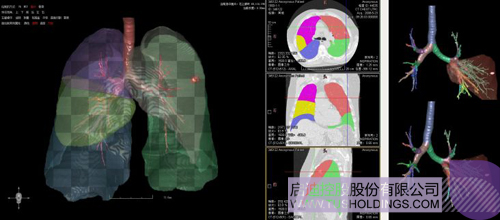

神州德信在醫療影像人工智能方面的核心技術為:智能影像=機器學習+計算/微分幾何+深度學習。

(1)計算/微分幾何用于分析、量化、可視化影像中所變現的各類組織以及病變等形態特征,機器學習主要對影像以及相關病變進行分類等定性分析并輔助一些定量分析,是服務臨床的一個重要模塊或者環節但不是唯一的環節。上述兩者在影像分析中互為補充、彼此增強,構建了神州德信智能影像分析的技術基礎。

(2)在整個智能影像分析中,核心技術建立在對醫學圖像深刻理解的基礎之上,相關幾何分析技術可以對數據進行有效增強和預處理,提升目前深度學習的學習能力、盡可能降低深度學習對樣本規模、多樣性和標注的要求,有效改變當前以深度學習為代表的“人工智能”重在 “人工”而不是“智能”的特點。

完整的三維影像智能分析技術;

完整的三維可視化以及相關建模、幾何分析技術;

肺動脈栓塞輔助診斷